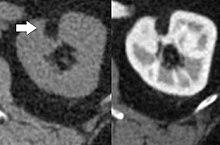

Angiomyolipoma in both kidneys (arrows) in computer tomography. The tumours are hypodense (dark) due to fat content

CT scan of a renal angiomyolipoma. It involves the renal cortex, and has an attenuation of less than 20 HU on the Hounsfield scale, which are typical characteristics.[2]